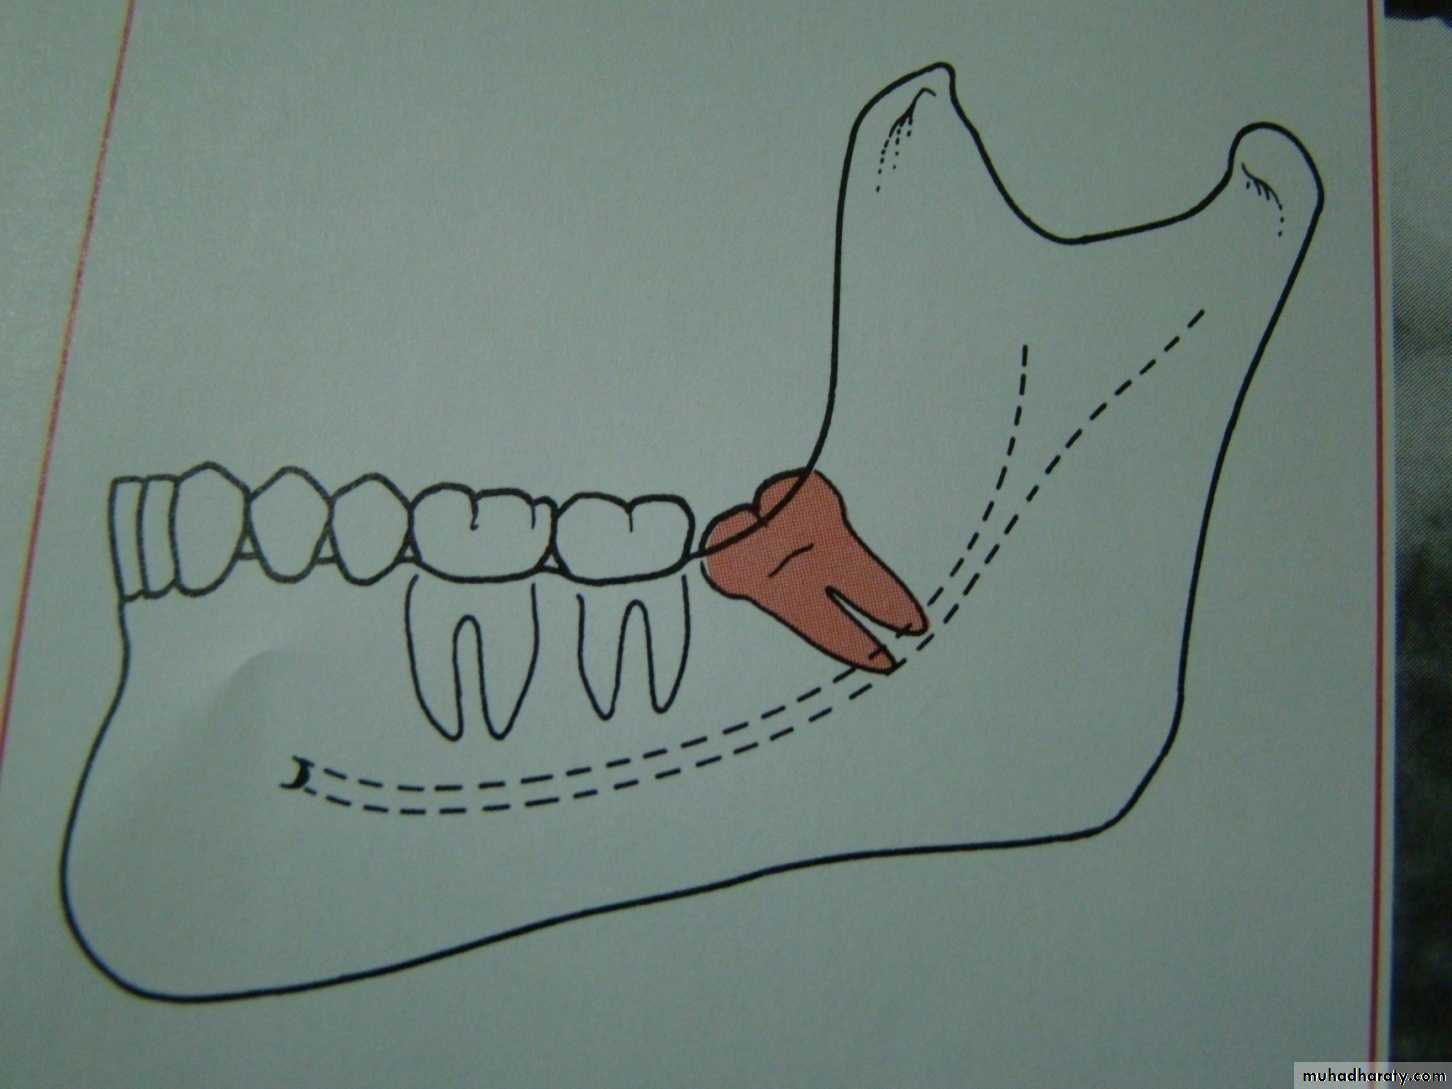

Winters classification of impacted lower third molarMesio angular

Disto angular

Horizontal

Vertical

Inverted

Transverse

Buccoversion

Linguversion